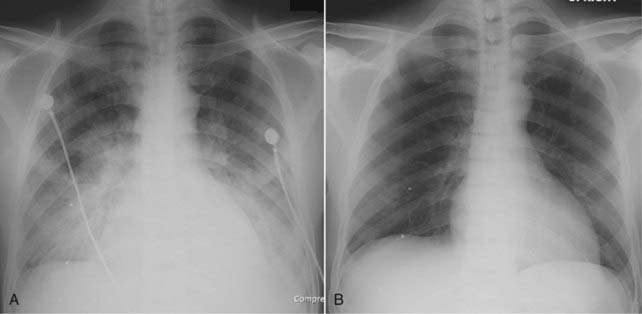

imageYou can estimate the size of the cardiac silhouette on the frontal chest radiograph using the cardiothoracic ratio, which is a measurement of the widest transverse diameter of the heart compared to the widest internal diameter of the rib cage (from inside of rib to inside of rib at the level of the diaphragm) (Fig. 9-1).

image In most normal adults at full inspiration, the cardiothoracic ratio is less than 50%. That is, the size of the heart is usually less than half of the internal diameter of the thoracic rib cage.

Figure 9-1 The cardiothoracic ratio.

To estimate the cardiothoracic ratio, the widest diameter of the heart (upper double arrow) is compared to the widest internal diameter of the thoracic cage from the inside of rib to the inside of rib (lower double arrow). The widest internal diameter of the thorax is usually at the level of the diaphragm. The cardiothoracic ratio should be less than 50% in most normal adults on a standard PA frontal radiograph taken with an adequate inspiration (about nine posterior ribs showing).